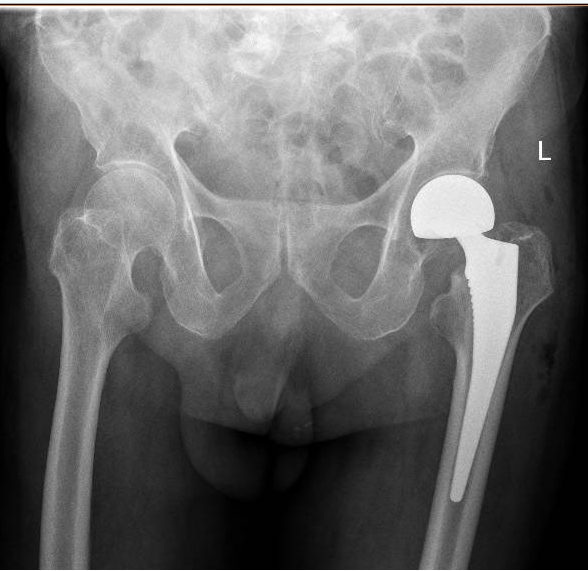

今年3月初,王大爺不慎在家中摔倒,左腿痛到無法下床,家人趕緊將老人送到市中醫(yī)醫(yī)院骨科救治。到院后,醫(yī)院立即啟動綠色通道,讓老人快速入院、接受全面檢查,并進(jìn)行多學(xué)科會診后制定了詳細(xì)手術(shù)方案,王大爺入院的第二天,便進(jìn)行了手術(shù)。

“王大爺入院時,檢查發(fā)現(xiàn)左側(cè)股骨頸骨折,也就是我們常說的‘髖關(guān)節(jié)骨折’。老人發(fā)生髖關(guān)節(jié)骨折,也被稱為‘人生最后一次骨折’,死亡率近60%。讓人痛心的是很多老人是死于骨折后長期臥床導(dǎo)致的并發(fā)癥?!笔兄嗅t(yī)醫(yī)院骨科主治醫(yī)師吳東海介紹,老人發(fā)生骨折后,如果采用保守治療,長期臥床容易發(fā)生壓力性損傷、尿路感染、肺部感染等并發(fā)癥,生活質(zhì)量幾乎無從談起,更有可能因并發(fā)癥威脅到生命。比較好的解決方案是盡快進(jìn)行手術(shù),讓老人重新站起來,減少并發(fā)癥的發(fā)生,提高生活質(zhì)量,也減輕家人的負(fù)擔(dān)。

“通過團(tuán)隊的默契配合,王大爺?shù)氖中g(shù)我們僅用30多分鐘就順利完成,術(shù)中出血量不到50ML,做到了手術(shù)時間少,出血少,把各種風(fēng)險降低到最小化。手術(shù)后,配合術(shù)后護(hù)理、內(nèi)科治療、中醫(yī)手法康復(fù)等,讓老人獲得了快速康復(fù)?!眳菛|海說,隨著技術(shù)的進(jìn)步,越來越多的高齡患者得益于先進(jìn)的綜合治療方法,這將讓更多的高齡患者提高生活質(zhì)量,重新煥發(fā)新活力。